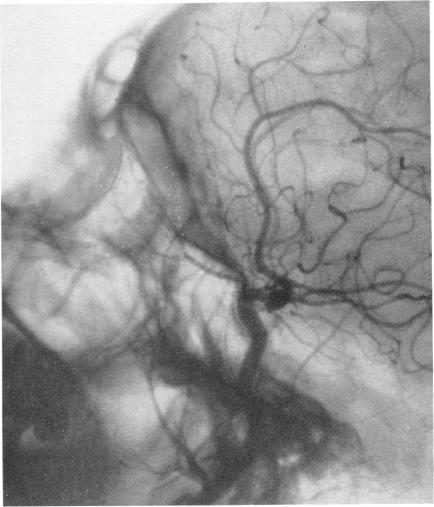

Arteriography and phlebography in the diagnosis of orbital affections.

Bull N Y Acad Med. 1968 Apr;44(4):409-30.